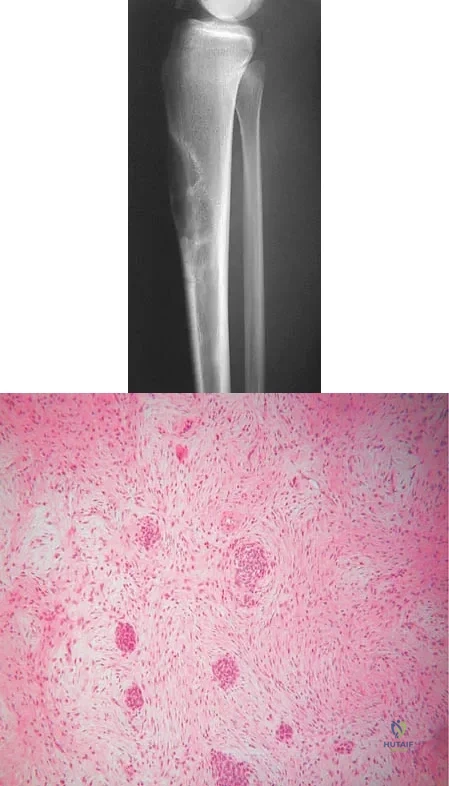

Question 6High Yield

An 18-year-old boy reports increasing pain with weight bearing on his right leg and at night. Examination reveals swelling around the right midcalf. Radiographs and an MRI scan are shown in Figures 13a through 13c, and a biopsy specimen is shown in Figure 13d. What is the preferred treatment?

Explanation